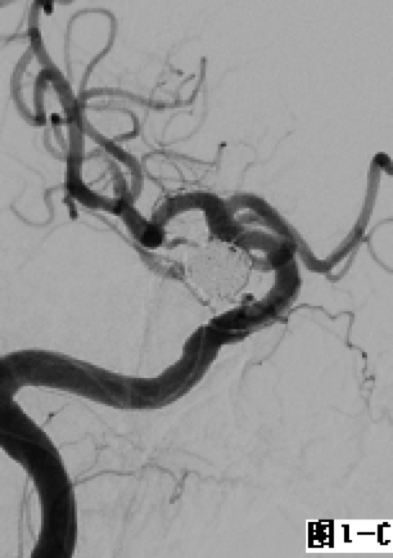

图1 采用经典式双微导管技术栓塞右侧后交通不规则形态动脉瘤。A.DSA显示右侧后交通动脉“葫芦形”不规则动脉瘤;B.在合适的工作角度下降2根微导管置入瘤体内不同位置;C.通过2根微导管交替填塞微弹簧圈,至填塞致密。